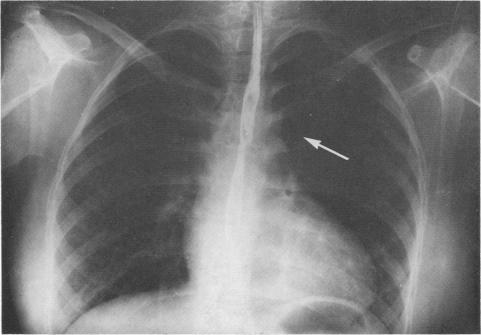

SURGICAL MANAGEMENT OF PERSISTENT LEFT SUPERIOR VENA CAVA.

Cardiovasc Dis. 1974 Jan;1(1):17-23.